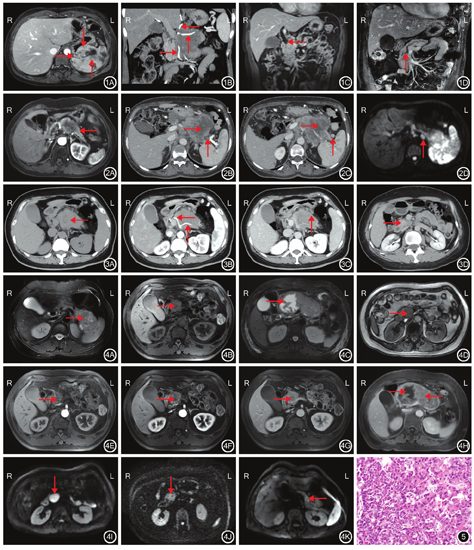

21例患者中,7例行单纯CT检查,11例行单纯MRI检查,3例行CT联合MRI检查。(1)肿瘤形状:21例患者肿瘤均为单发,其中17例呈圆形或类圆形,4例形态不规则呈团块状。(2)肿瘤发生部位:21例患者中,胰头部6例,胰头部和胰体部2例,胰体部2例,胰体尾部4例,胰尾部4例,壶腹部3例。(3)肿瘤最大径为(43±29)mm,范围为11~129 mm。(4)邻近器官侵犯:21例患者中,10例侵犯邻近器官,其中2例侵犯邻近胃、脾及左侧肾上腺(图1A),4例侵犯十二指肠,3例侵犯十二指肠及胆总管,1例侵犯脾脏。(5)血管侵犯:12例患者侵犯脾动脉、脾静脉,其中1例同时侵犯肝总动脉和肠系膜上动脉(图1B),1例同时侵犯腹腔干根部。(6)胰管和胆管侵犯:8例患者发生胰管和胆管扩张,其中4例胆管及上游胰管扩张(图1C、图1D),4例单纯胰管扩张。(7)淋巴结转移:2例患者肿瘤周围淋巴结肿大(图2)。(8)其他情况:7例患者肿瘤中心伴囊变坏死。4例患者胰腺实质萎缩(图2)。2例患者脾静脉瘤栓形成(图2)。2例患者合并囊肿。1例患者肝脏多发转移。

10例行CT检查患者:(1)CT检查平扫显示10例肿瘤主体以实性部分为主,呈等密度,其中3例肿瘤似有边界,2例肿瘤周围有假包膜,5例肿瘤中心见低密度坏死区。(2)CT检查动脉期显示:7例肿瘤实性部分强化低于正常胰腺组织,3例肿瘤动脉期强化高于正常胰腺组织。(3)CT检查延迟期显示:7例肿瘤延迟期密度稍低或等于正常胰腺组织,整体表现为轻度渐进性强化;3例肿瘤延迟期密度稍高于或等于正常胰腺组织。见图3。

(1)14例患者行MRI检查平扫显示:8例病灶呈较均匀稍长T2和稍长T1信号,6例病灶呈长T2和等T1为主的混杂信号。4例病灶内可见囊变坏死区 ,10例病灶未见囊变坏死区。14例病灶均未见反相位信号减低。(2)12例患者行MRI动态增强检查,其中11例病灶呈轻度渐进性强化;1例病灶呈明显混杂强化,延迟期廓清。与邻近正常胰腺组织比较,DWI(b=800 s/mm2)示6例呈高信号,6例呈稍高信号,2例呈晕环样高信号。14例病灶表观扩散系数值为(1.22±0.14)x10-3 mm2/s。见图4。